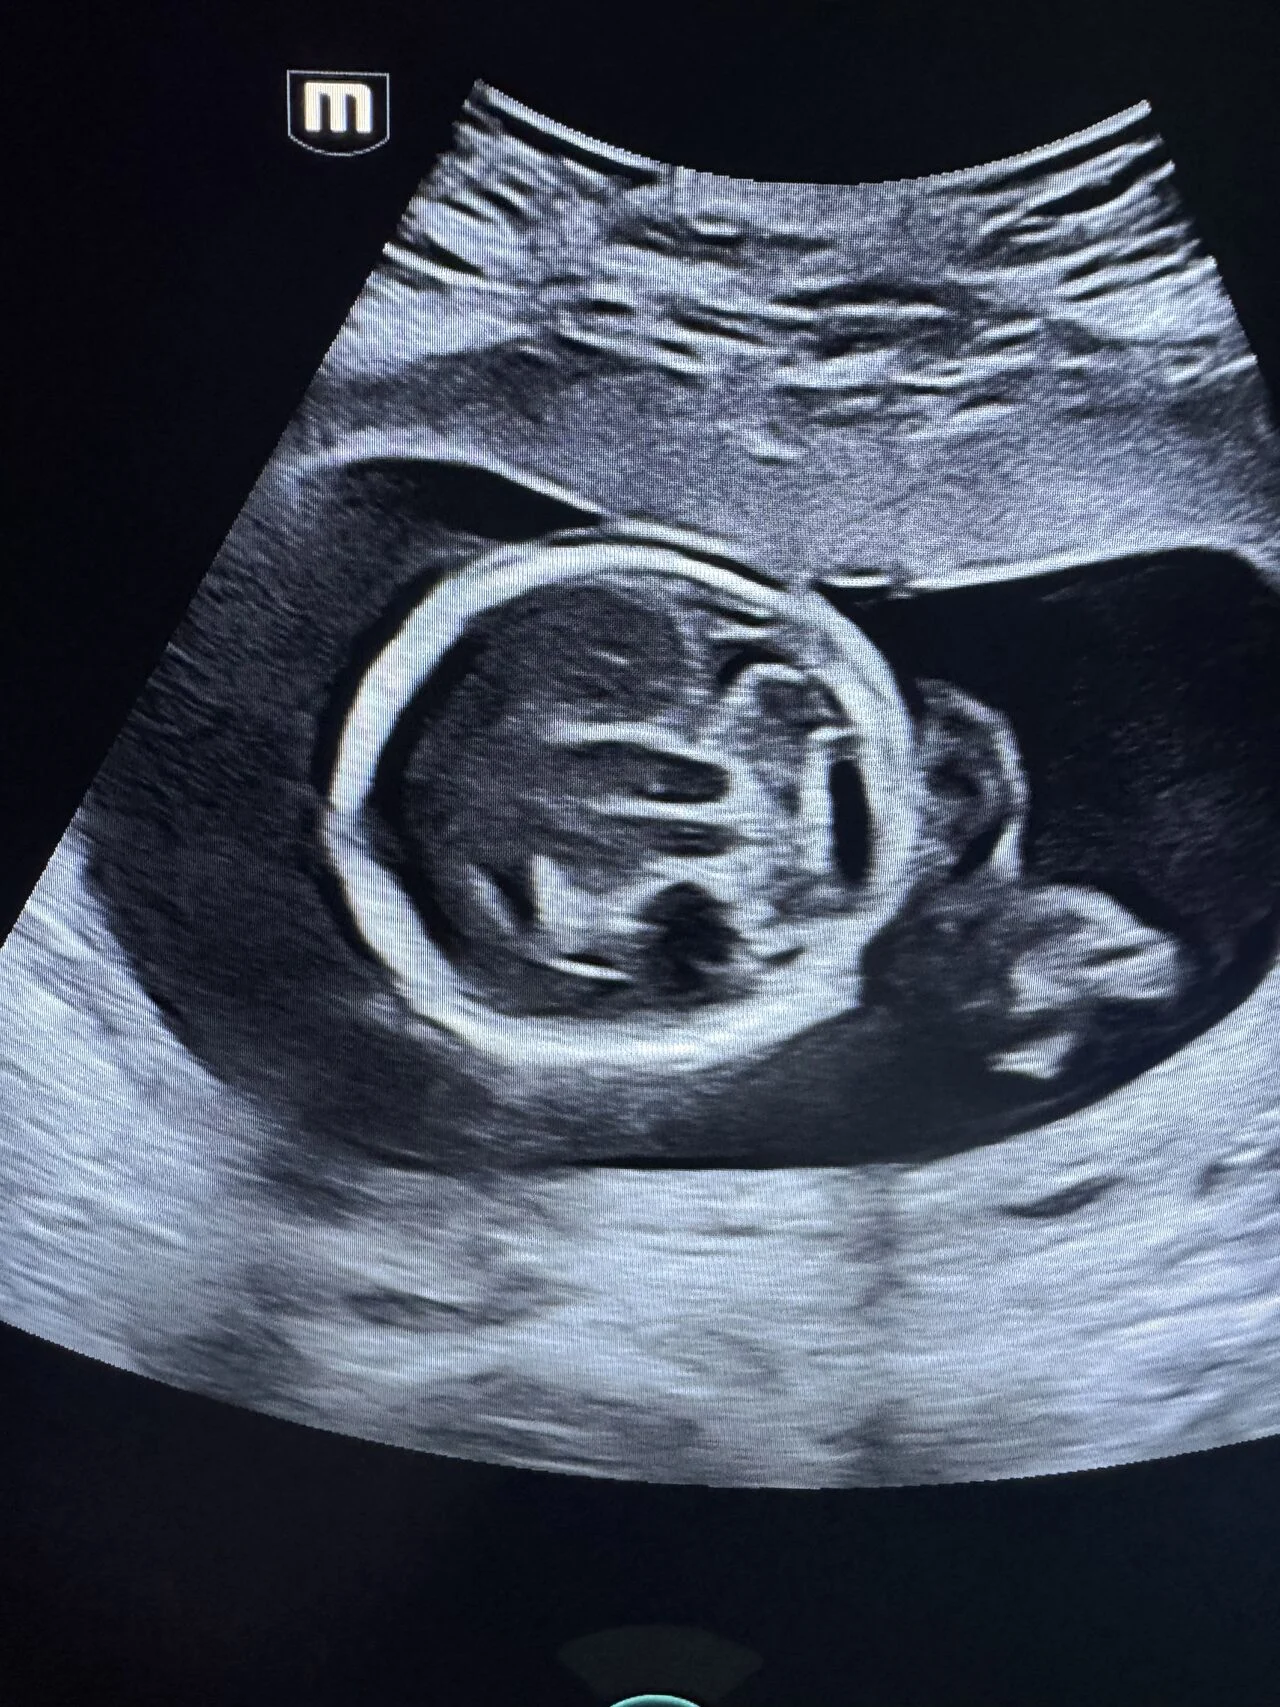

“Fetal Anomaly Case | Semilobar Holoprosencephaly

A prenatal ultrasound case demonstrating features of semilobar holoprosencephaly.

Key neurosonographic findings:

- Single midline ventricular cavity

- Fused thalami

- Partial absence of interhemispheric fissure

- Absent cavum septum pellucidum